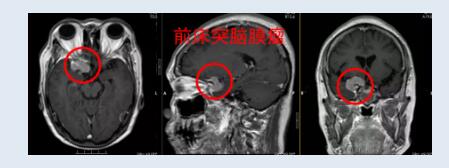

欧阳辉教授为黄阿姨安排了相关检查。颅脑磁共振(MRI)检查结果证实黄阿姨的脑部确实长了肿瘤,初步怀疑是右侧前床突脑膜瘤。黄阿姨拿到结果时,难以置信地问:“本以为只是老花眼,怎么脑子就长了肿瘤呢?”

“这个肿瘤刚好长在视神经管周围,肿瘤压迫视神经就会影响视力。肿瘤长得跟鸽子蛋般大小,并从前床突凸入视神经管,包绕视神经,已经严重压迫视神经,才导致眼睛几乎失明,而且肿瘤还有继续增大的趋势,必须尽快手术切除。”欧阳辉教授耐心地解析。

欧阳辉教授指出:前床突脑膜瘤是起源于前床突和蝶骨内侧1/3的脑膜瘤,该部位解剖结构深且居于要害部位,毗邻颈内动脉及其分支、视神经、视交叉、动眼神经、滑车神经、垂体柄、海绵窦、眶上裂、外侧裂等重要结构,手术非常具有挑战性。

前床突脑膜瘤根据起源部位分为三型:1型起源于前床突下方,肿瘤易推移、包绕颈内动脉、颈内动脉分叉、大脑前、中动脉,因缺乏蛛网膜分隔,肿瘤与颈内动脉及其分支难以分离。II型起源于前床突的上方和外侧方,由于肿瘤与血管之间有众多蛛网膜分隔,即使肿瘤包绕血管,也大多能安全分离。III型起源于视神经孔,肿瘤易突入视神经管内,并延伸至前床突尖端。